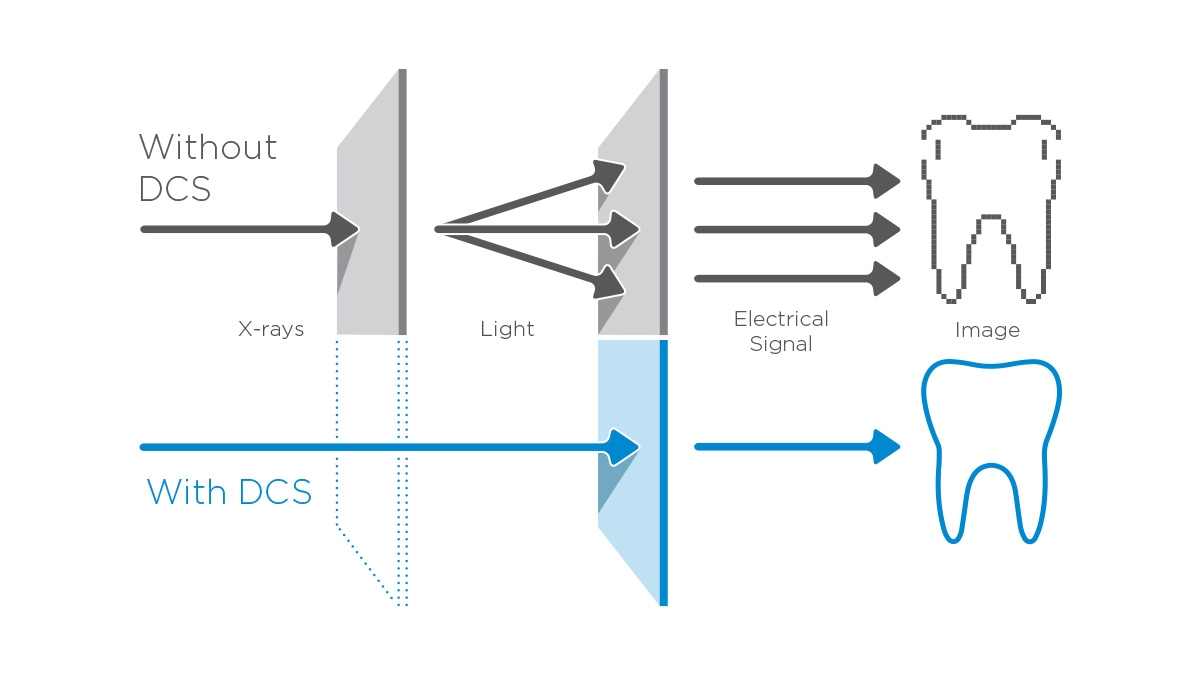

We developed a 10-point concept for easy patient positioning and X-ray imaging. Our concept is primarily about two things: high image quality and comfort for the patient and the assistant. This concept supports and provides the tools needed to ensure high-quality images for treatment analysis and focuses on ergonomics and comfort for the patient and assistant. The patented bite block technology, for example, automatically establishes the correct inclination of the patient's head, positioning the patient in the occlusal plane, partnering with the 3 point head fixation and firm handles to ensure stable positioning-limiting unnecessary correction scans.